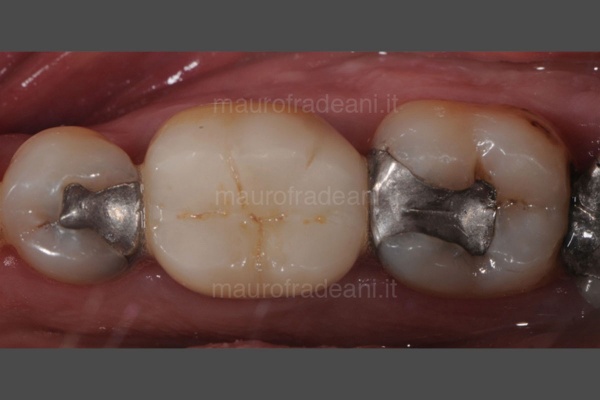

Replacement of amalgam fillings

1/4: In cases of tooth decay infiltration under old dental amalgam fillings, it is necessary to replace them with composite material which, in addition to a greater biocompatibility, guarantees ideal esthetic results.

2/4: Due to the toxicity of the mercury it contains, the removal of the amalgam must be carried out safely, protecting the patient with special devices such as the rubber dam which, while guaranteeing the isolation of the operating field, allows to have an ideal control of all the materials removed as well as the fluids inside the oral cavity.

3/4: Removing the old filling exposes the decayed dental tissue, which is carefully removed.

4/4: Together with a greater biocompatibility, the composite offers an ideal esthetics to the treated teeth as it perfectly blends with the dental enamel.